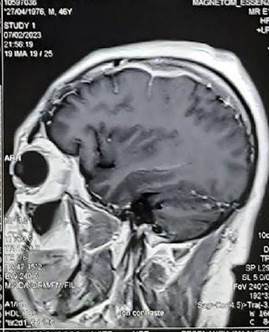

Debido a la persistencia de los síntomas, 12 meses antes del ingreso se realizó una biopsia de meninges estereotáxica en otra institución la cual fue reportada como tejido conectivo de aspecto hipertrófico con focos granulomatosos crónicos de células linfomononucleares, histiocitos con necrosis caseosa y coloración alcohol acido resistente positiva para Mycobacterium tuberculosis (BK+), concluyendo en paquimeningitis con granulomas crónicos caseificantes (figura 2). Once meses antes del ingreso, en esa misma institución se inició tratamiento para tuberculosis con esquema 1 (rifampicina 600 mg/d, isoniacida 300 mg/d, etambutol 1 200 mg/d, pirazinamida 1 500 mg/d por 2 meses, seguido de 10 meses con rifampicina 600 mg/d e isoniacida 600 mg/d), y corticoterapia (Inició con dexametasona 24 mg/d, disminuyendo progresivamente 4 mg por semana). Después de un mes de haber iniciado tratamiento, cursó con cefalea a predominio frontal de moderada intensidad y se realizó RM cerebral donde se evidenció engrosamiento paquimeníngeo en la convexidad frontoparietal izquierdo de 8 mm (figura 3).

Engrosamiento paquimeníngeo en la convexidad frontoparietal izquierda de 8 mm.